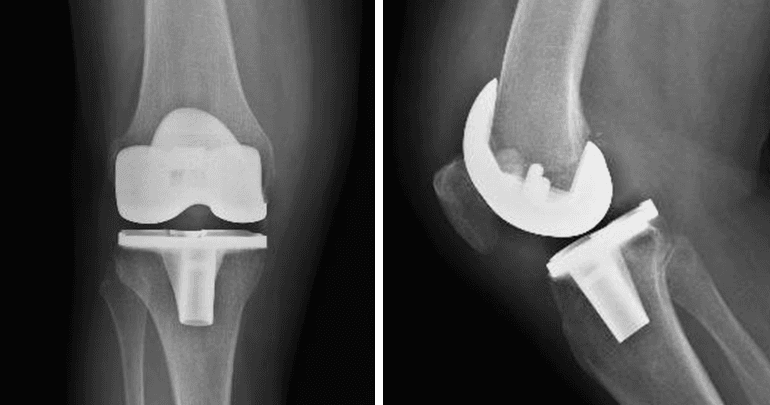

L’intervento di artroprotesi di ginocchio prevede la sostituzione chirurgica del femore distale e della tibia prossimale con protesi metalliche, associate a materiali plastici e/o ceramici. Quando necessario, si può includere anche la protesizzazione della rotula. Lo scopo principale di questa procedura è ripristinare un’articolazione stabile e funzionale, migliorando la capacità di movimento del paziente e alleviando il dolore, con conseguente miglioramento della qualità della vita.

Oggi sono disponibili diversi tipi di protesi, adattabili alle varie esigenze funzionali dei pazienti e ai diversi scenari osseo-legamentosi. Per le protesi totali si distinguono in generale impianti con conservazione (Cruciate Retaining – CR) o sacrificio (Posterior Stabilized – PS) del legamento crociato posteriore, con ulteriori sottogruppi di inserti a seconda delle necessità del paziente e della tecnica di impianto adottata. Per situazioni più complesse o per revisioni protesiche si possono utilizzare impianti semivincolati o a cerniera.